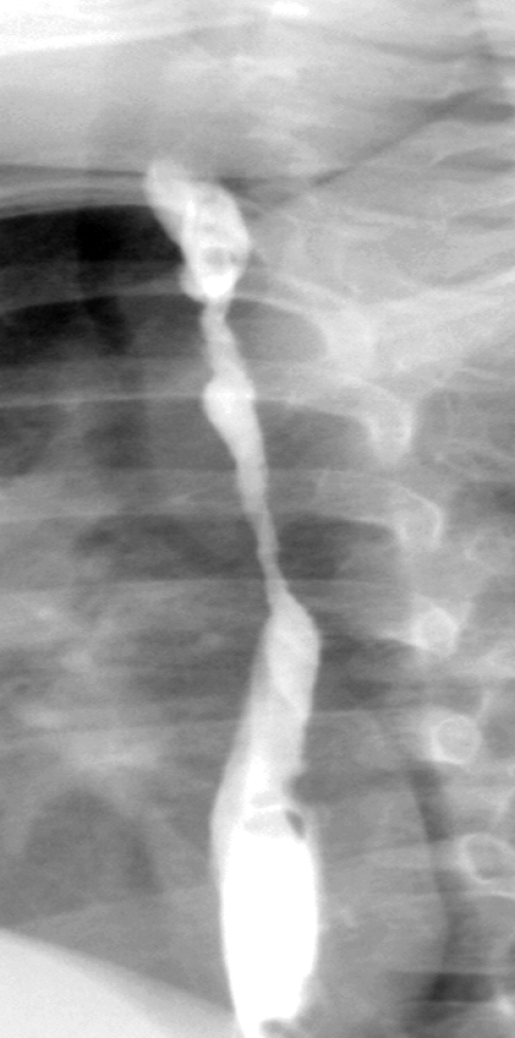

Acid ingestion (HCL). Diffuse burns and contraction/shrinkage of both the esophagus and stomach (Courtesy Dr. V. Penopoulos)